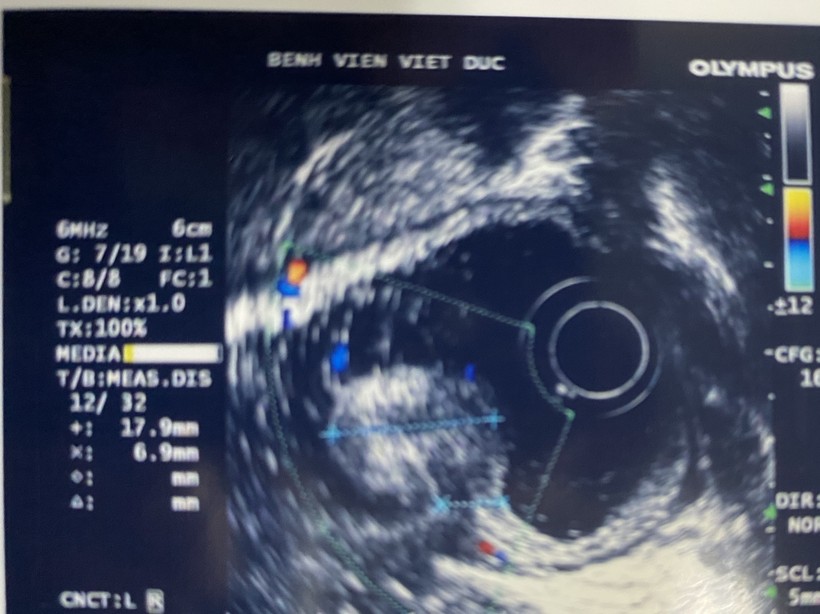

Ngay sau đó, các bác sĩ đã tiến hành siêu âm nội soi để xác định khối u đã phát triển đến lớp nào trong thành ống tiêu hóa để đưa ra phương pháp điều trị phù hợp. Sau khi hội chẩn với các bác sĩ nội soi, ê kíp phẫu thuật đã quyết định thực hiện phương pháp can thiệp nội soi hiện đại “cắt tách niêm mạc” – ESD (Endoscopic Submucosal Dissection) để loại trừ tổn thương, bảo tồn dạ dày cho người bệnh. Nếu thủ thuật nội soi thất bại thì sẽ phẫu thuật cắt dạ dày sau.

| Hình ảnh siêu âm của bệnh nhân (Ảnh: Bệnh viện Hữu nghị Việt Đức) |

BS. Chu Nhật Minh - Trưởng khoa Nội soi Tiêu hóa, Bệnh viện Hữu nghị Việt Đức - cho biết: Bệnh nhân T. vào viện trong tình trạng bị tổn thương dạng u lan tỏa - LST (laterally spreading tumor) theo phân loại Paris 2008 về các tổn thương tiền ung thư với cấu trúc bề mặt gồm các biểu hiện như: phì đại, quăn queo, nhìn thấy mạch máu nhỏ, phân bố không đều, chảy máu rỉ ở vài điểm, ranh giới rõ,… Các bác sĩ tiến hành nội soi cắt tách niêm mạc cho bệnh nhân.